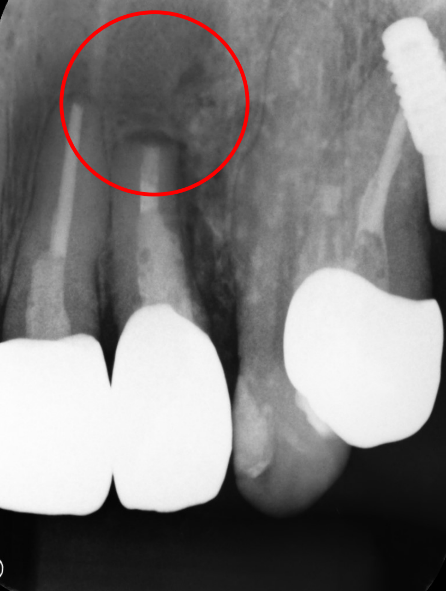

初診時

-

治療後

1年後

主訴

前歯の歯ぐきが腫れた。

治療の概要

根管治療では治らない歯に対して、根の先端を切除しそこから特殊な器具で穴をあけ、MTAという材料を充填し封鎖をはかりました。

1年後のレントゲンでは、根尖の病変がなくなり、骨ができています。